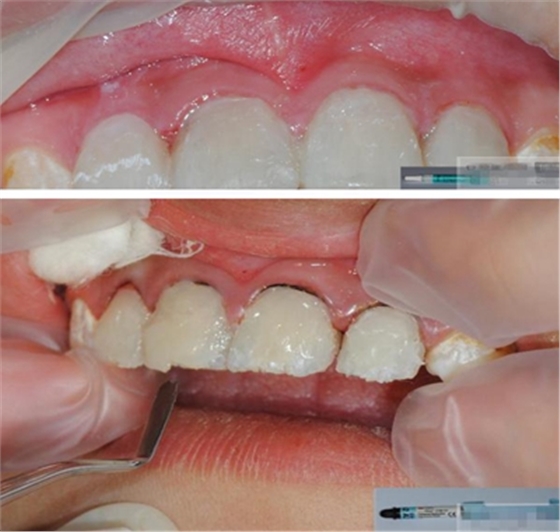

制作 背板

修復(fù)鄰壁

Hawe Sycamore Interdental Wedges——小楓木

切忌在近遠(yuǎn)中同時(shí)放置楔子,這樣會(huì)擠壓牙齒使其伸長,調(diào)合時(shí)會(huì)感覺修復(fù)體過高。如果近遠(yuǎn)中需要修復(fù)時(shí),可在一端放置楔子,修復(fù)后,再放置另一端